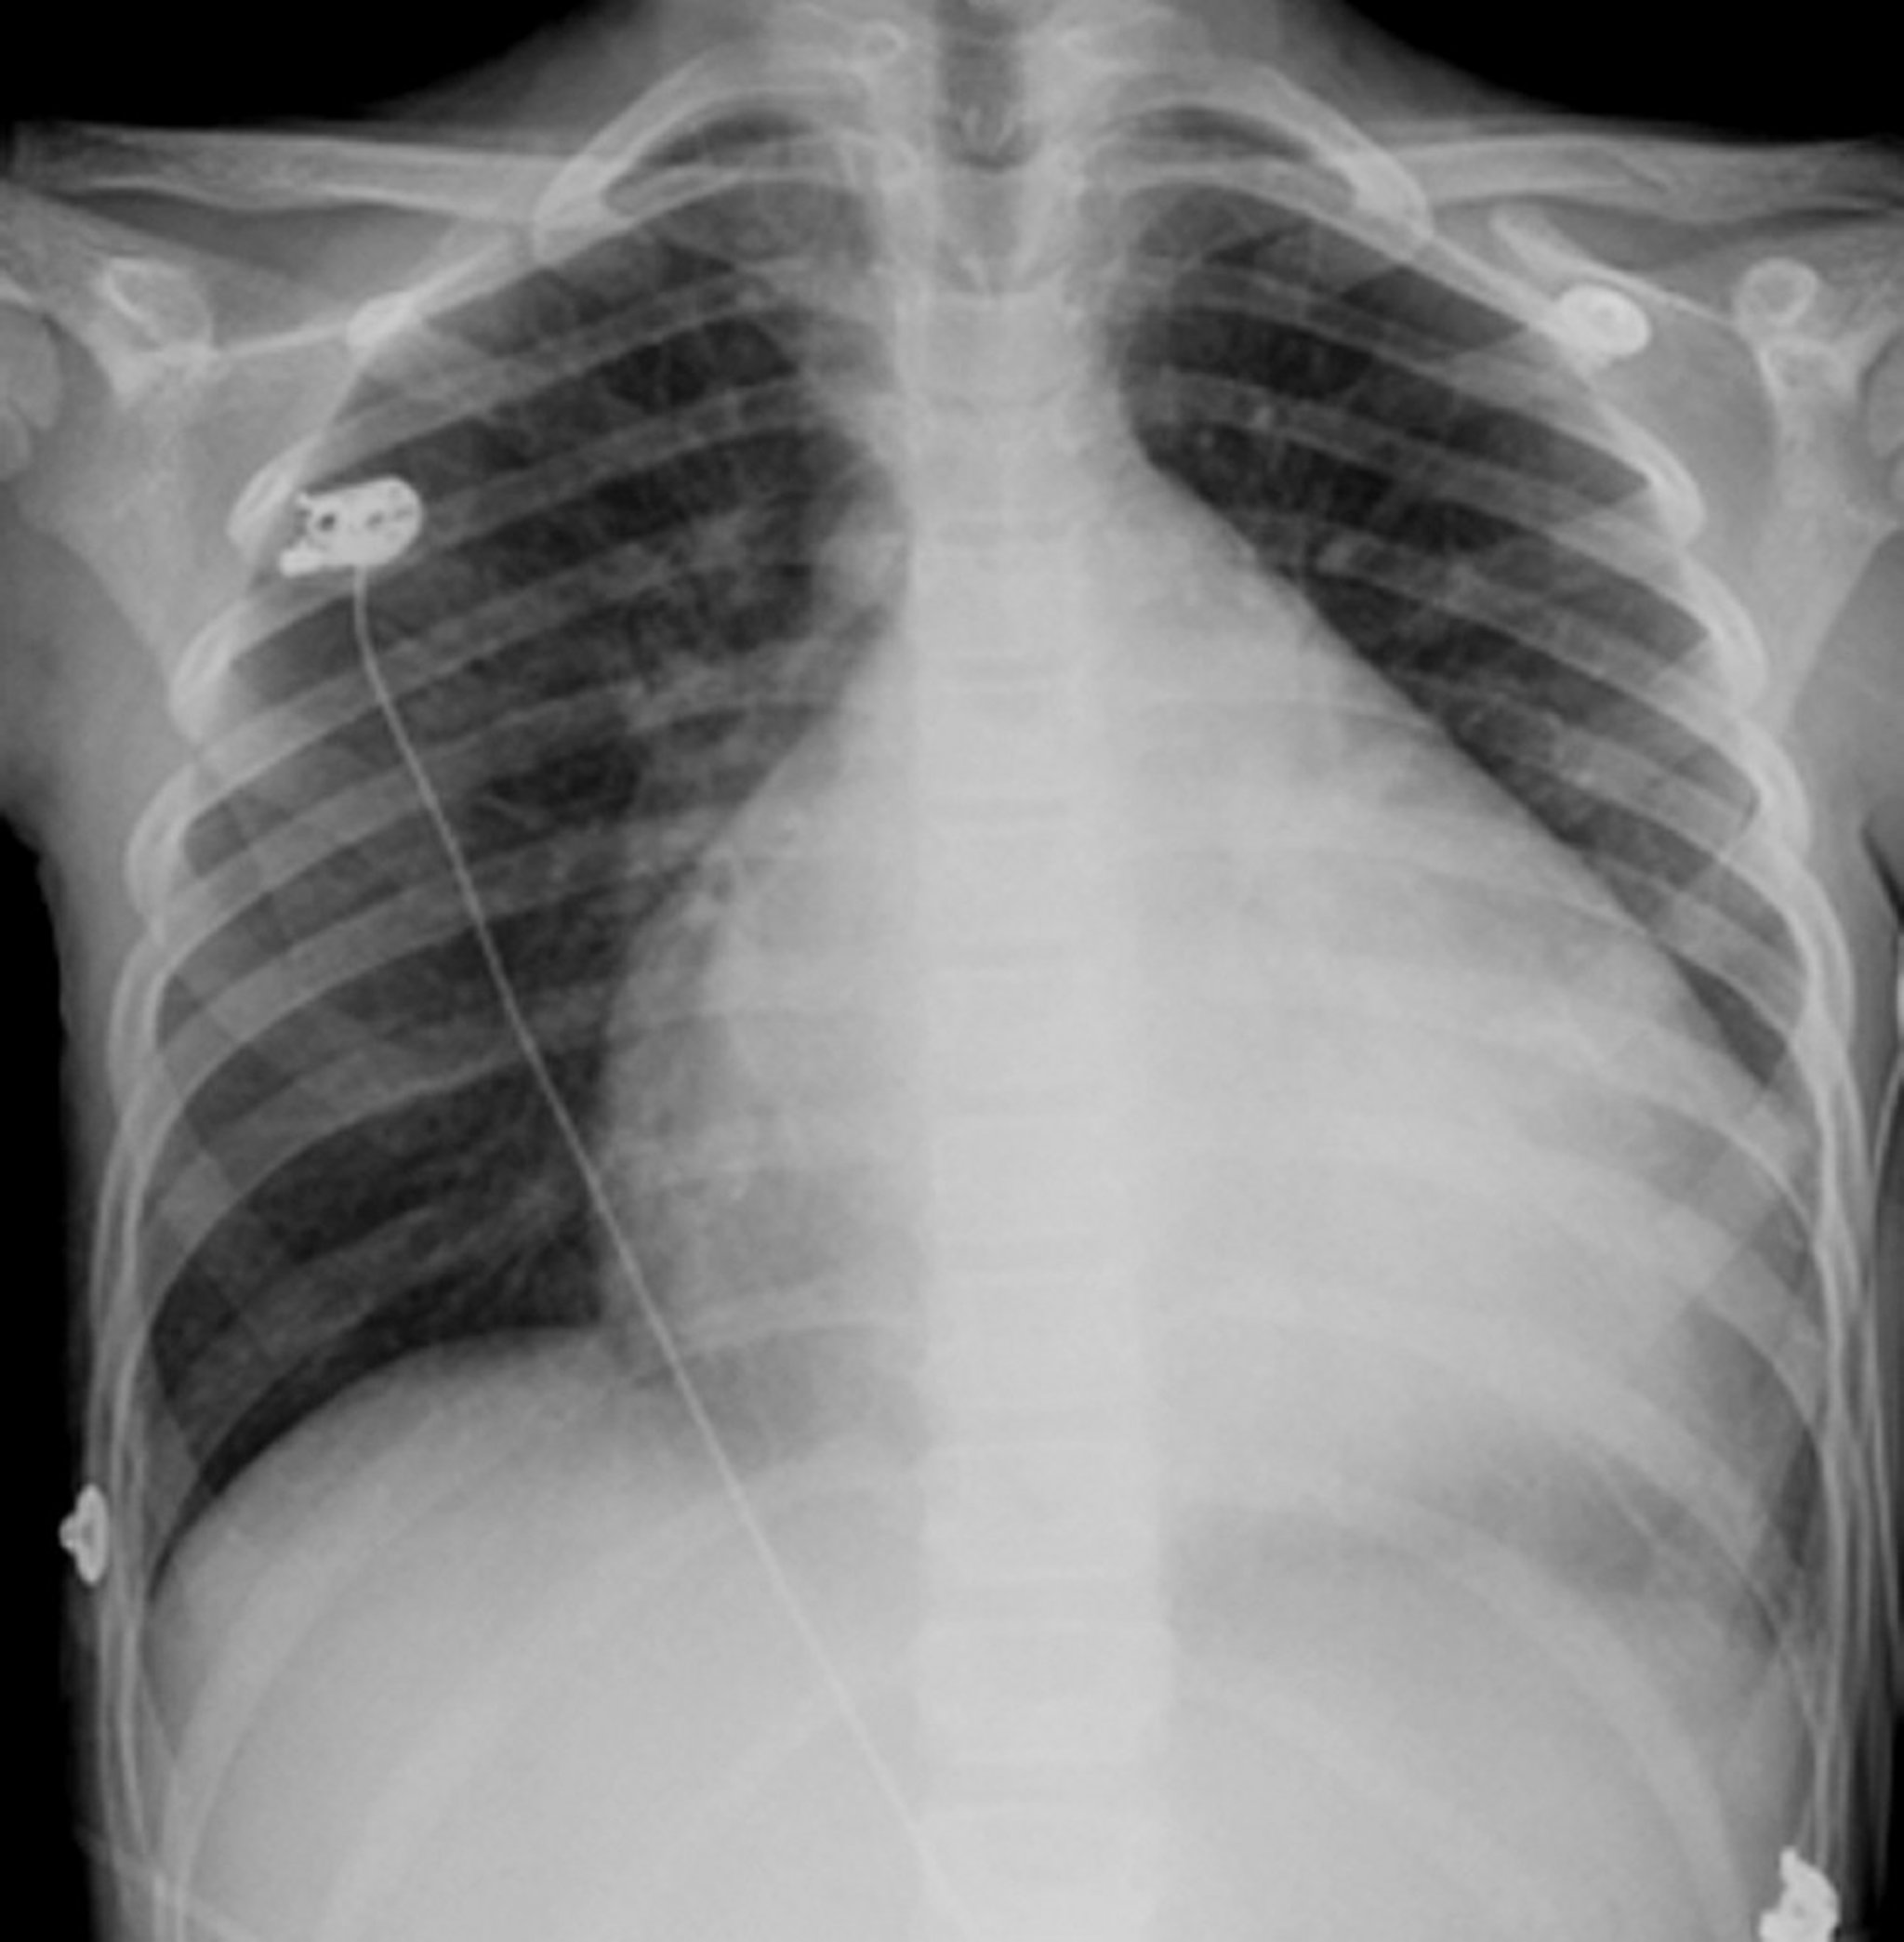

Jantung adalah struktur berbentuk bulat dan berwarna putih di tengah dada. Biasanya jantung memakan ruang kurang dari setengah dada, namun, pada orang ini yang mengalami pembesaran jantung (kardiomiopati), jantung hampir memenuhi 3/4 dimensi dada.

Sinar-x menunjukkan bentuk dan ukuran jantung dan garis bentuk pembuluh darah besar di paru-paru dan dada. Bentuk atau ukuran jantung yang tidak normal dan abnormalitas seperti endapan kalsium dalam pembuluh darah jadi mudah terlihat. Pemeriksaan sinar-x pada dada juga dapat mendeteksi informasi tentang kondisi paru-paru, terutama apakah pembuluh darah di paru-paru abnormal dan apakah ada cairan di dalam atau di sekitar paru-paru.

Sinar-X dapat mendeteksi pembesaran jantung, yang sering kali disebabkan oleh gagal jantung atau gangguan katup jantung. Sinar-X terkadang dapat membantu dalam diagnosis perikarditis konstriktif dengan mendeteksi endapan kalsium pada kantung yang menyelimuti jantung (perikardium).